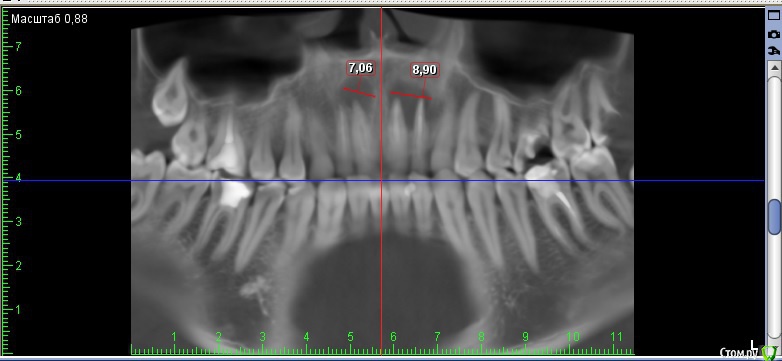

Andre_ Опубликовано 22 октября, 2015 Поделиться Опубликовано 22 октября, 2015 Верхней челюсти кисты, если быть точнее. Терапевт пробовал перепроходить - цемент. Пациент - молодой парень, крайне хочется, чтобы ушёл с зубами, хотя бы временными. Какой бы вы план действий преложили? Ссылка на комментарий

diesel87 Опубликовано 22 октября, 2015 Поделиться Опубликовано 22 октября, 2015 Верхней челюсти кисты, если быть точнее. Терапевт пробовал перепроходить - цемент. Пациент - молодой парень, крайне хочется, чтобы ушёл с зубами, хотя бы временными. Какой бы вы план действий преложили?iv_cyst_maxilla.jpgПерепроходите еще раз Ссылка на комментарий

DmitrySH Опубликовано 22 октября, 2015 Поделиться Опубликовано 22 октября, 2015 Есть смысл пробовать ещё? Да вы еще и не попробовали толком. Передайте пациента эндодонтисту со скопом и будет всем счастье.Под микроскопом цемент расломбировать в прямом канале.. вообще никаких проблем. Поводов для хирургии на данный момент нет. 7 Ссылка на комментарий

Дмитрий Никитюк Опубликовано 23 октября, 2015 Поделиться Опубликовано 23 октября, 2015 Забудьте про диагноз "киста", это моветон. Подобные диагнозы можно ставить только после гистологии. Есть диагноз "апикальный периодонтит". Соответственно и подход к лечению при таком диагнозе не предполагает на первом этапе никакой хирургии, только ретрит. Затем динамическое наблюдение и принятие решения по хирургическому лечению, в случае неэффективности консервативного. 5 Ссылка на комментарий